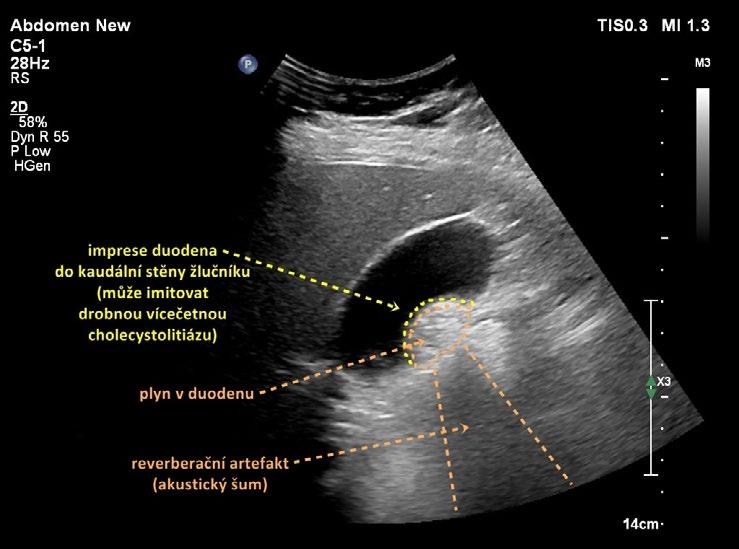

Postprandiálně se mírně dilatuje ductus hepatocholedochus. Potrava přítomná v duodenu ztěžuje zobrazení distálního a intrapankreatického hepatocholedochu. Artefakty z duodena, které naléhá na spodní stěnu žlučníku, mohou imitovat patologii stěny žlučníku či drobnou vícečetnou cholecystolitiázu. Za duodenem však nevzniká typický dorzální akustický stín jako za konkrementy, ale reverberační artefakty v podobě hypoechogenního akustického „šumu“ (obr. 1.2).

Obr. 1.2 Imprese duodena do kaudální stěny žlučníku